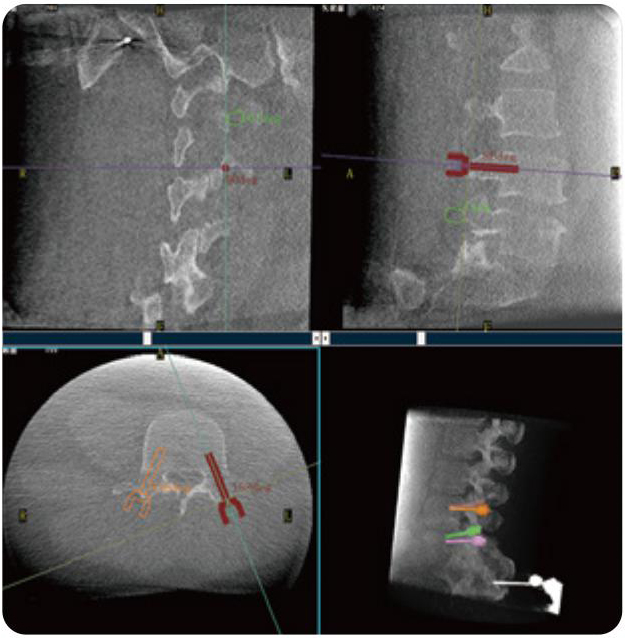

PL300B可應用于多節(jié)段脊柱外科手術,輔助醫(yī)生定位病灶部位,為脊柱外科手術(經(jīng)皮椎體成形術、椎弓根螺釘內固定術等術式)提供術前手術流程規(guī)劃、入釘位置、角度可視化引導,模擬仿真入釘輔助。

PL300B搭配普愛醫(yī)療自主研發(fā)生產(chǎn)的平板3D C形臂,借助一體化自適應配準( 軌跡配準)技術,通過追蹤C形臂三維采集軌跡,自動完成圖像坐標建立和系統(tǒng)坐標配準。配準精度更高,操作步驟少,系統(tǒng)運作效率高。